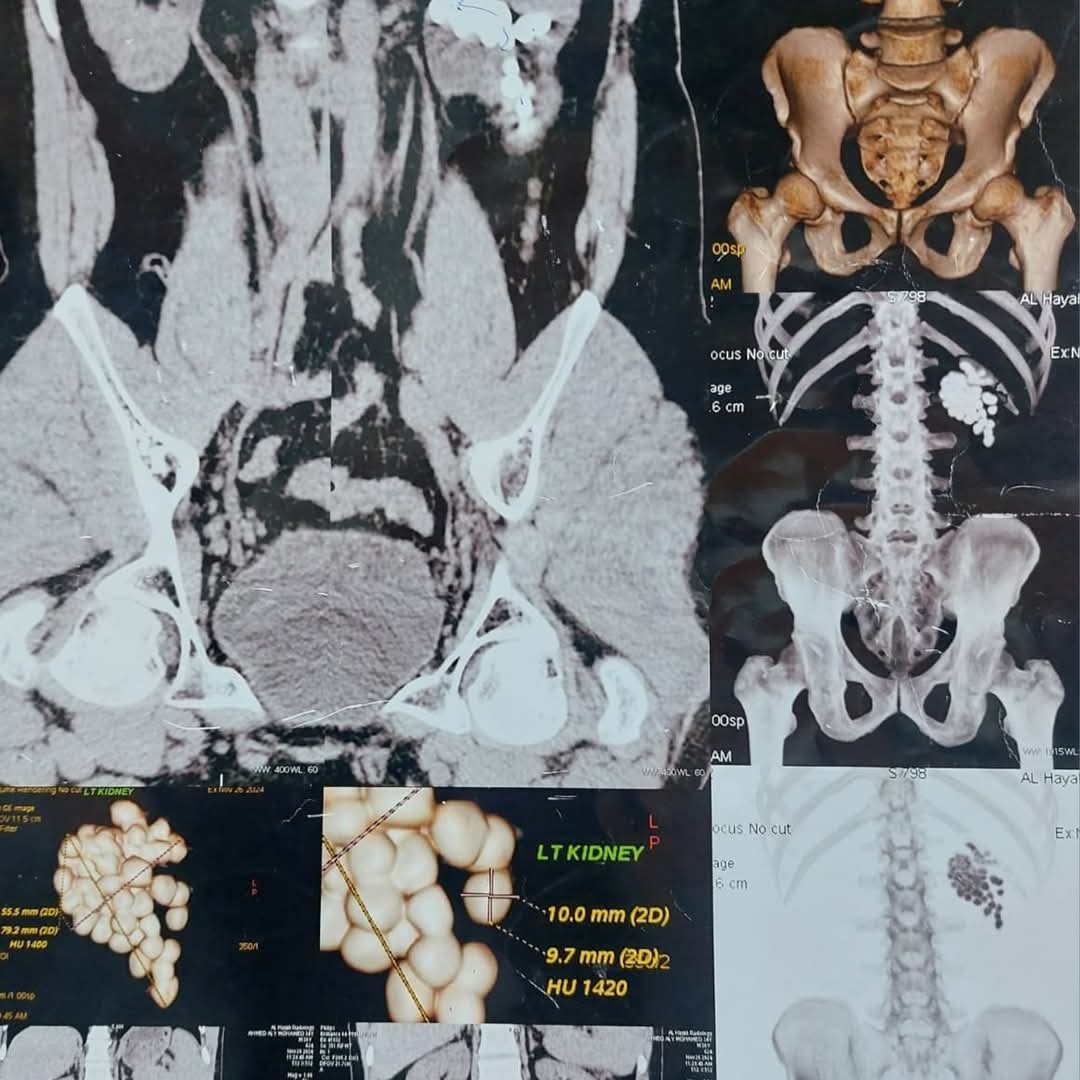

وأوضح دكتور مصطفى عبد الرازق رئيس قسم المسالك البولية أن المريض وصل إلى المستشفى وهو يعاني من آلام متكررة وارتفاع في نسبة الأملاح، وبعد إجراء الفحوصات اللازمة تبيّن وجود عدد كبير من الحصوات المتجمعة في حوض الكلية اليسرى، مما استدعى التدخل الجراحي الفوري للحفاظ على سلامة الكلية.

وتم تجهيز المريض للعملية وإجراء التخدير العام، ثم بدأ الفريق الطبي العمل بتقنية منظار الكلية عن طريق الجلد، وهي من أحدث الأساليب التي تسمح بإزالة الحصوات الكبيرة والمتعددة بدون فتح جراحي. وتم عمل فتحة جراحية صغيرة لا تتجاوز سنتيمترًا واحدًا للوصول إلى الكلية، ثم تفتيت الحصوات باستخدام تقنيات التفتيت الهوائي والليزر تبعًا لطبيعة كل حصوة.

استغرقت العملية نحو ساعتين، تمكن خلالها الفريق الطبي من استخراج الحصوات كاملة مع التأكد من تنظيف حوض الكلية تمامًا لمنع تكرار المشكلة مستقبلًا، كما تم وضع أنبوب تصريف مؤقت لضمان خروج السوائل بشكل آمن بعد العملية. وخرج المريض من غرفة العمليات في حالة مستقرة، بينما تمت متابعة علاماته الحيوية داخل الإفاقة، وسط تحسن ملحوظ في حالته العامة ووظائف الكلى.